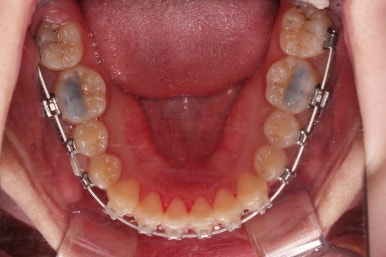

연산동교정치과 교정장치 부착 직후의 모습입니다.

장치가 보이는 느낌이나 입매가 바뀌는 느낌 참고 바랍니다.

이번 환자분은 교정장치를 부착했다해도 거의 입매가 바뀌지 않는 분입니다.

매우 급속도로 가지런해지고 있죠?

대신에 초기 단계에서는 가지런하게 하는데만 초점을 맞추게 되는데 앞니가 뻗치거나 송곳니가 양옆으로 벌어져 보이는 양상을 보입니다.